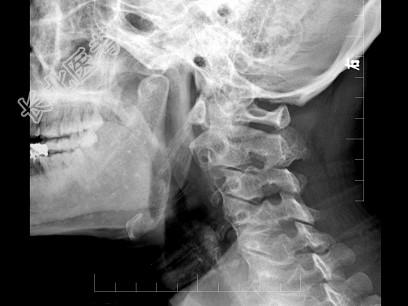

- 多项选择题女,37岁, 咽部异物感、咽痛伴反射性耳痛、头颈部不适近1年余,如图所示, 下列描述正确的是 ( )

A、左侧茎突长约3.5cm

B、右侧茎突长约4.0cm

C、双侧茎突过长综合征

D、右侧茎突过长综合征

E、正常茎突